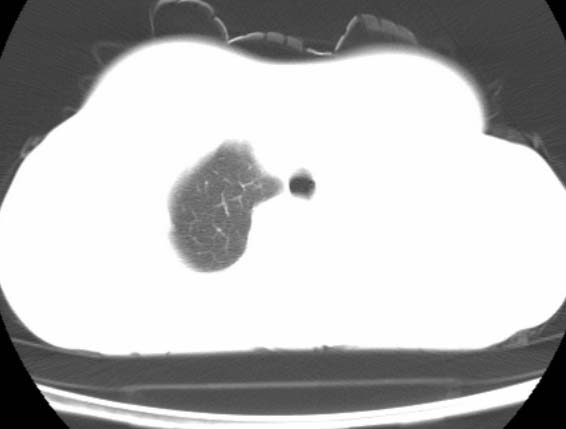

女  20岁。一月前咳血,诊“肺结核”抗痨治疗一月后,咳血停止,现复查。病人精神好。前后ct片对比未见明显变化。既往体检“正常”

1)考虑左肺结核并肺不张、支气管扩张。2)纵隔疝。

考虑左肺结核,左肺毁损,纵膈左偏,既往体检正常不可靠,tb一个月也不会这个样子的,有钙化,应该病程较长,冰冻三尺非一日之寒!

左肺发育不全。

考虑左肺结核,左肺毁损,纵膈左偏,既往体检正常不可靠,tb一个月也不会这个样子的,有钙化,应该病程较长,冰冻三尺非一日之寒

结核,左肺毁损。